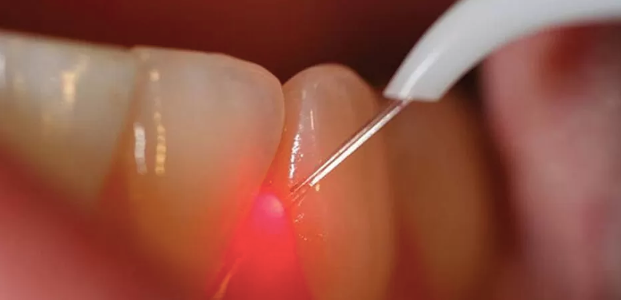

LASER stands for Light Amplification by the Stimulated Emission of Radiation. The instrument creates light energy in a very narrow and focused beam. This narrow focused beam produces a reaction when it hits the tissue, allowing it to remove or shape the tissue.

• Treating gum diseases